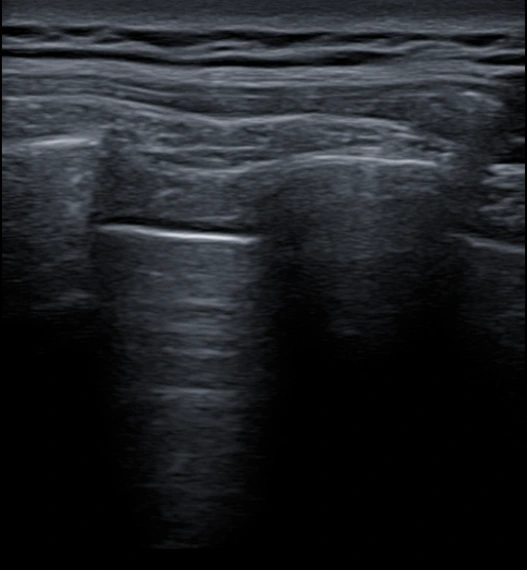

초음파 검사를 추가로 시행했고,

역시나 늑간신경에 염증이 생긴 상태였어요.

그래서 저희는 SI(초음파유도하)주사치료를 시행해요.

초음파로 정확한 병변 부위를 실시간으로 확인하면서

염증이 생긴 늑간신경 주변에 약물을 주입하는 방식이에요.

"폐 근처라서 위험하지 않나요?"

맞아요. 늑간신경은 폐 바로 옆에 위치해 있어서

자칫 잘못하면 기흉의 위험이 있어요.

그래서 이 치료는 임상 경험이 풍부한 통증의학과 전문의가

초음파를 보면서 신중하게 시행해야 해요.

%EA%B7%B8%EB%A6%BC7.png?type=w966

<이 환자분도 원인 부위에 정확히 치료받았답니다. ^^>